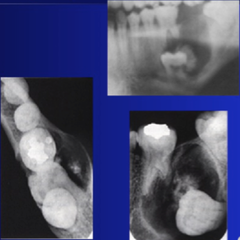

dentigerous cyst

-young adult -well defined unilocular radiolucency around crown of unerupted impacted or developing tooth